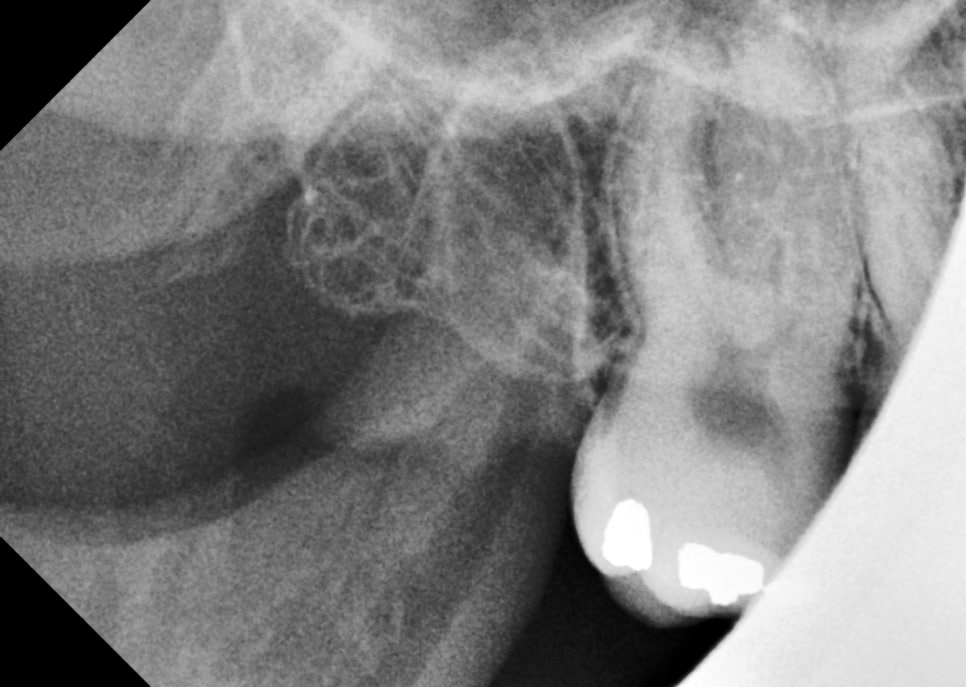

10일 뒤 내원하셔서 실밥을 제거하면서 반대쪽도 위, 아래 사랑니를 발치했어요.

촬영일 : 251121

오른쪽도 뿌리가 부러지지 않고 신경관의 손상 없이 깔끔하게 제거되었어요.

해당 부위에도 지혈제를 넣어 출혈을 줄이고, 상처가 안정적으로 회복될 수 있도록 했습니다.